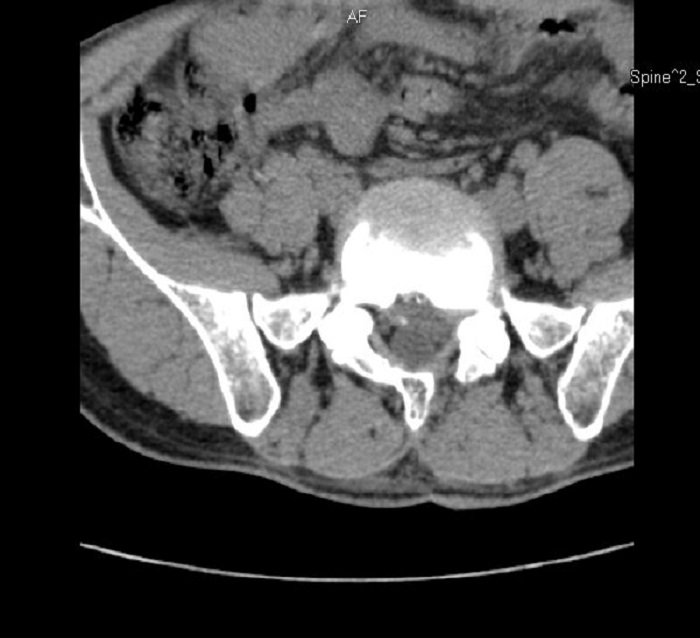

術后